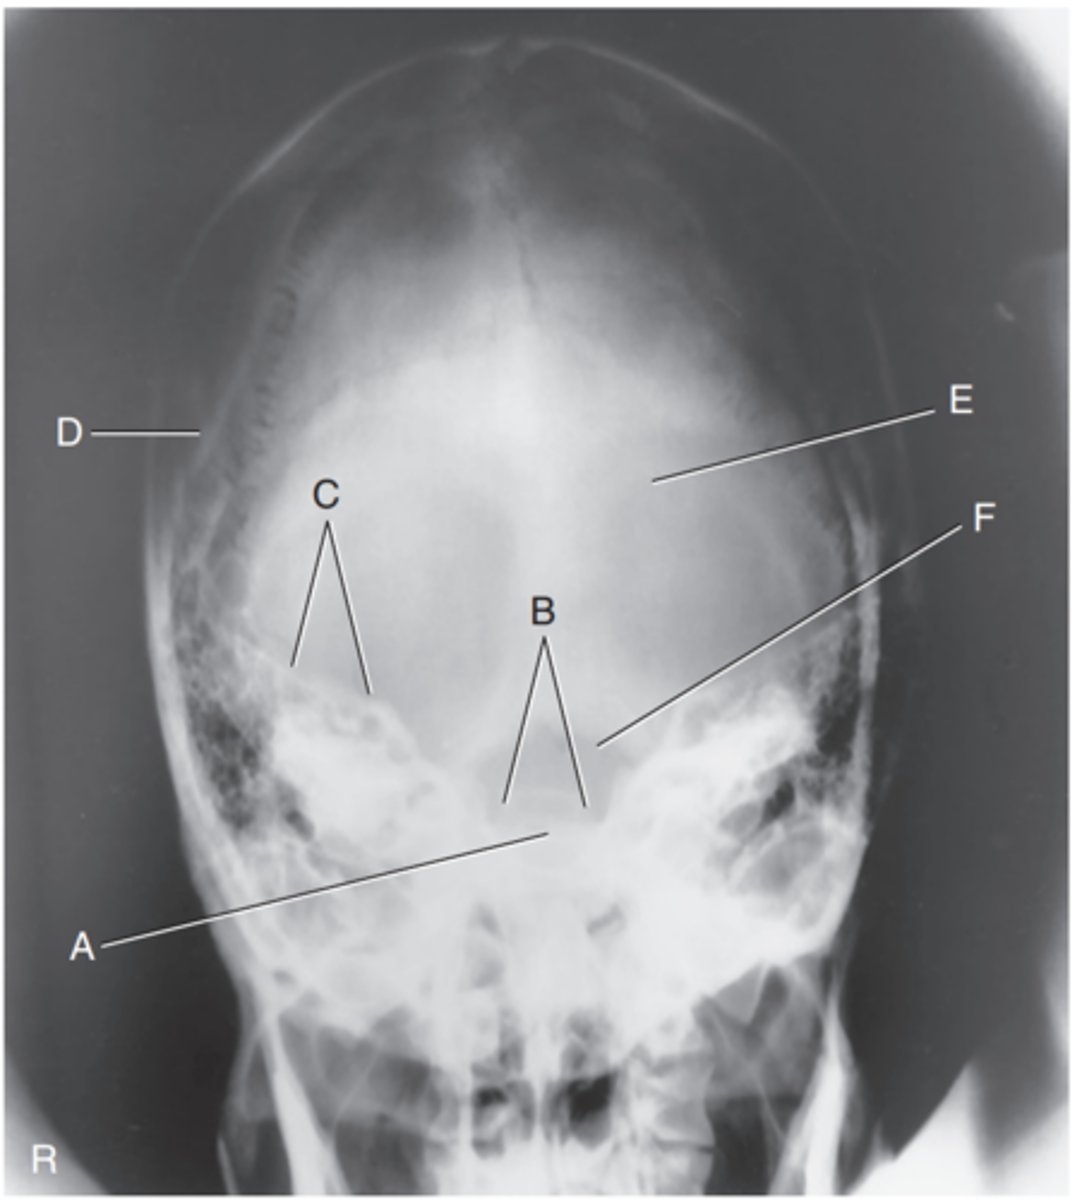

Supraorbital margin of right orbit

Label A

Crista galli of ethmoid

Label B

Sagittal suture

Label C

Lambdoidal suture

Label D

Petrous ridge

Label E